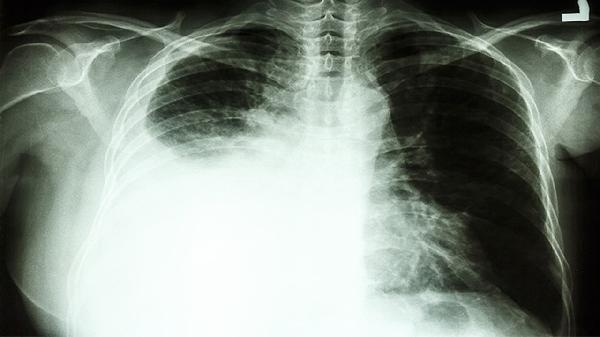

肿瘤与气管的毗邻关系是手术关键。若肿瘤仅压迫气管但未侵犯管壁,通常可完整切除;若已浸润气管软骨或黏膜层,需联合气管袖状切除术。术前需通过支气管镜和三维重建CT明确浸润深度。

纵隔淋巴结转移是手术禁忌证之一。PET-CT和纵隔镜检查可判断N2期以上转移,若存在对侧纵隔或锁骨上淋巴结转移,则需优先考虑放化疗而非手术。

根据肿瘤位置选择肺叶切除+气管成形术或全肺切除术。达芬奇机器人手术可提高气管吻合精度,对紧贴气管的肿瘤,术中需联合快速病理确认切缘阴性。

CT检查是诊断肺癌的重要手段之一,但不能单独确诊肺癌,确诊需结合病理活检、支气管镜等检查。 1、影像学筛查 CT...